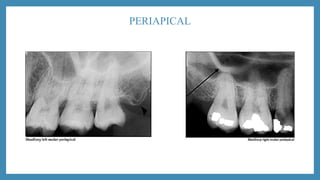

PERIAPICAL

• Periapical